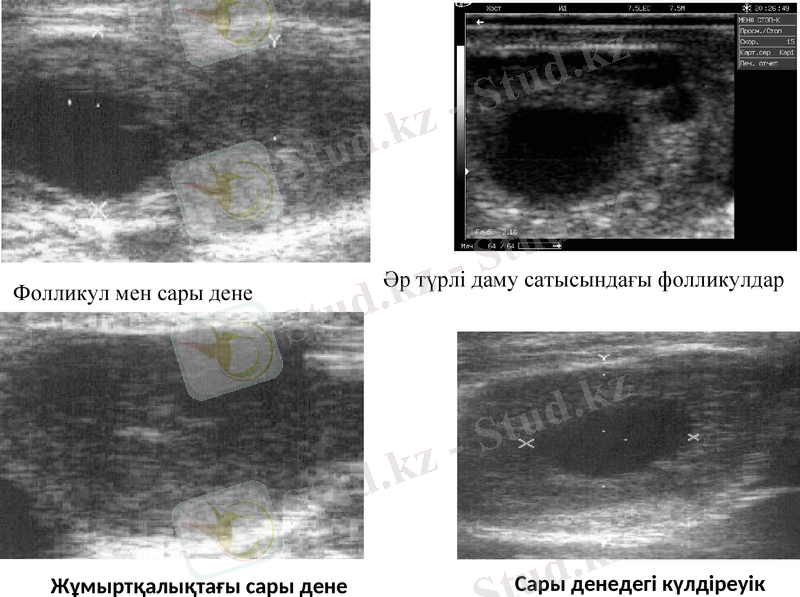

Фолликул мен сары дене

Әр түрлі даму сатысындағы фолликулдар

Жұмыртқалықтағы сары дене

Сары денедегі күлдіреуік